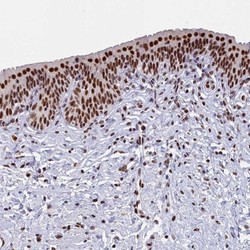

Supportive validation

- Submitted by

- Novus Biologicals (provider)

- Main image

- Experimental details

- Immunohistochemistry-Paraffin: MOSPD3 Antibody [NBP1-85698] - Staining of human urinary bladder shows strong nuclear positivity in urothelial cells.